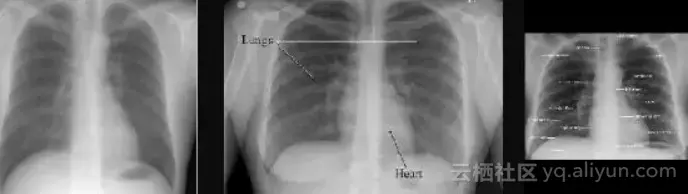

根据机构的不同,你可能会得到水平或垂直翻转的图像。它们可能包含反向像素值。他们可能会旋转。问题是,当处理一个巨大的数据集,比如5万到十万个图像时,你怎么能在没有医生指导的情况下发现这些畸变呢?

您可以尝试编写一些优雅的解决方案,比如:因为大多数胸部X光高度都比宽度高,因此在X光的两侧有黑色的边界,所以如果底部有超过50个黑色的像素行,那么它可能旋转了90度。

图2:这里只有中间的图像有经典的“黑色边框”

这些脆弱的规则不能解决上述问题。